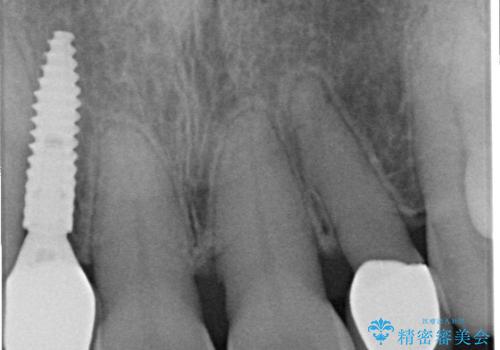

さらに、インプラント治療を併用することで、失われた歯の機能を取り戻し、より自然で健康的な見た目を実現します。インプラントは、人工の歯根を顎の骨に埋め込み、その上に歯の形をした人工歯を装着する治療法で、ブリッジや入れ歯に比べて違和感が少なく、しっかりとした咀嚼力を取り戻すことが可能です。

インプラント治療の注意事項(リスク・副作用など)

- 外科手術のため、術後に痛みや腫れ、違和感を伴います

- メンテナンスを怠ったり喫煙により、お口の中に大きな悪影響を及ぼすインプラント周囲炎等にかかる可能性があります

- 糖尿病、肝硬変、心臓病等の場合、インプラント治療ができない可能性があります

- 高血圧、貧血・不整脈等の場合、インプラント治療後に治癒不全を招く可能性があります